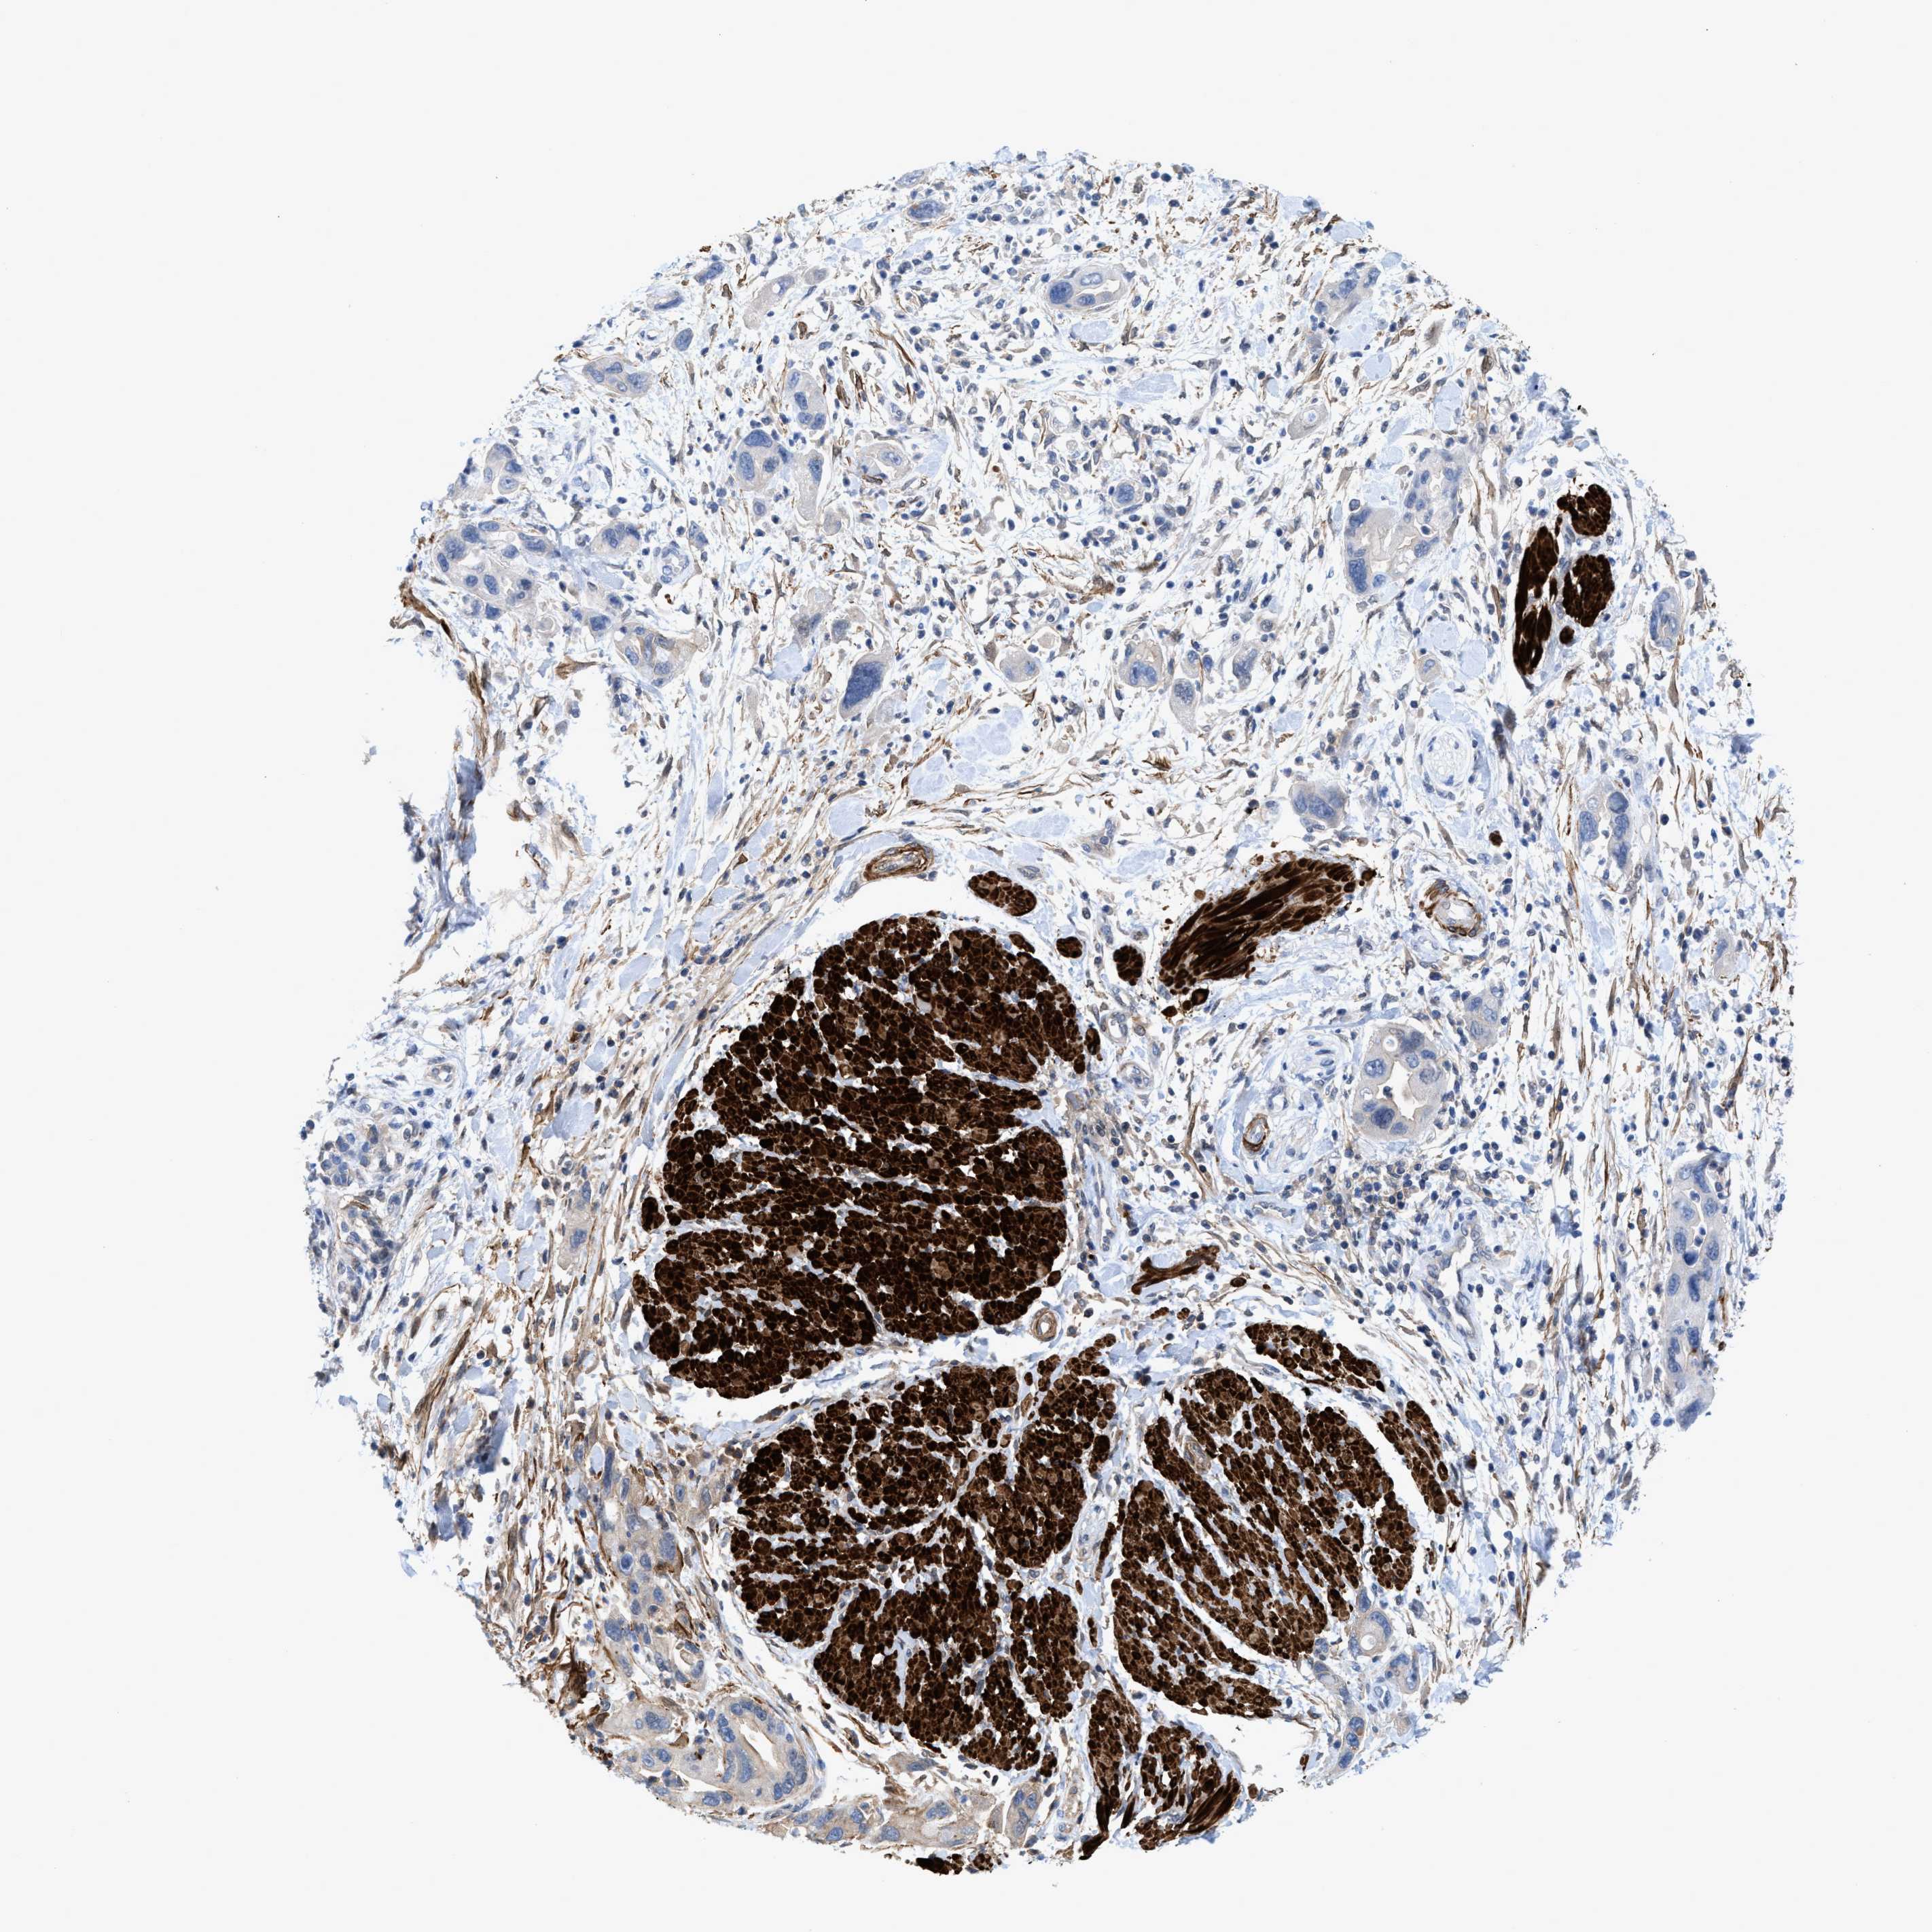

PANCREATIC CANCER - Protein expressioni

A mouse-over function shows sample information and annotation data. Click on an image to view it in a full screen mode. Samples can be filtered based on level of antibody staining by selecting one or several of the following categories: high, medium, low and not detected. The assay and annotation is described here.

Note that samples used for immunohistochemistry by the Human Protein Atlas do not correspond to samples in the TCGA dataset.

Antibody stainingi

Antibody staining in the annotated cell types in the current human tissue is reported as not detected, low, medium, or high, based on conventional immunohistochemistry profiling in selected tissues. This score is based on the combination of the staining intensity and fraction of stained cells.

Each image is clickable and will lead to virtual microscopy that enables deeper exploration of all samples and also displays staining intensity scores, fraction scores and subcellular localization as well as patient and tissue information for each sample.

Antibody HPA019467

Antibody HPA061657

Antibody CAB001447

Staining

High

Medium

Low

Not detected

Intensity

Strong

Moderate

Weak

Negative

Quantity

>75%

75%-25%

<25%

None

Location

Nuclear

Cytoplasmic/membranous

Cytoplasmic/membranous,nuclear

Adenocarcinoma, NOS